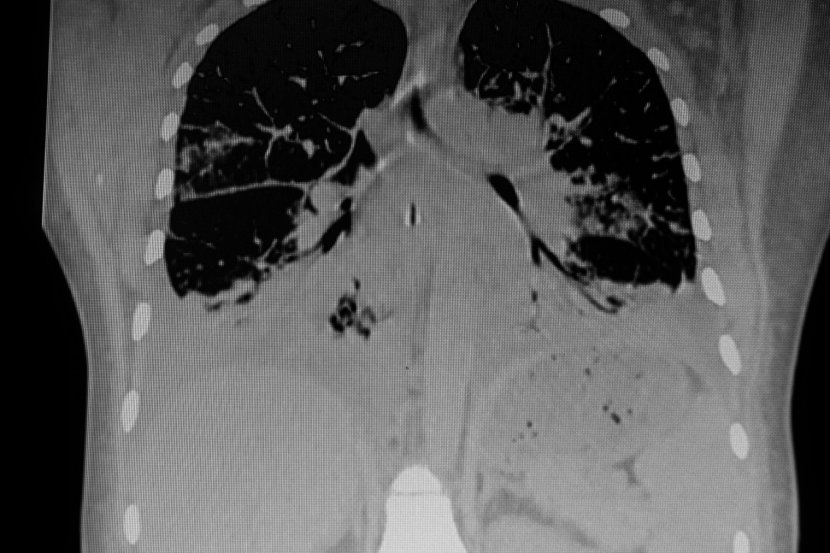

• snimanje – CT skener, MRI (magnetna rezonanca) ili kompjuterska tomografija visoke rezolucije (HRCT); HRCT snimci daju detaljniju sliku male površine pluća da bi se potražile određene bolesti pluća